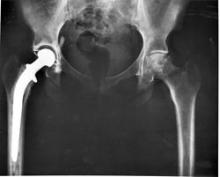

Hip replacement implants all work the same regardless of the material used, according to a new study.

The newer, metal-on-metal implants appear to be no more effective than older implants and may sometimes even be more problematic, the researchers said, according to HealthDay News.

“Metal-on-metal and ceramic-on-ceramic hip implants might not be associated with any advantage, compared with traditional bearings such as metal-on-polyethylene or ceramic-on-polyethylene,” lead researcher Dr. Art Sedrakyan, director of the Patient-Centered Comparative Effectiveness Program at Weill Cornell Medical College in New York City, told HealthDay.

While there is some evidence from three large national registries that higher rates of replacement surgery are associated with metal-on-metal implants, compared with metal-on-polyethylene implants, there is simply not enough information about these implants to determine if one type is better or safer than the other, Sedrakyan continued. Even for newer implants such as metal-on-metal or ceramic-on-ceramic bearings, their advantage over traditional implants is not clear, he told HealthDay.